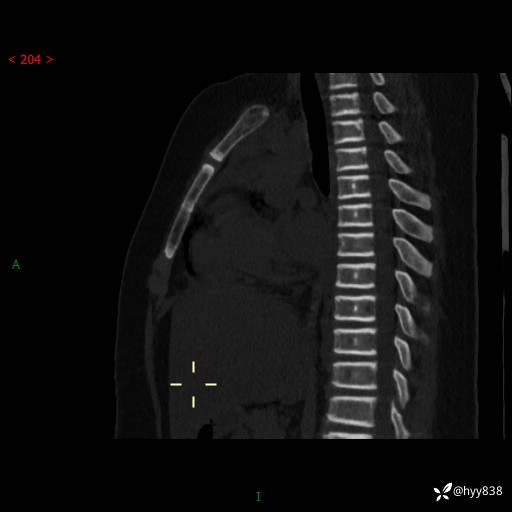

胸部CT脊柱MPR

img